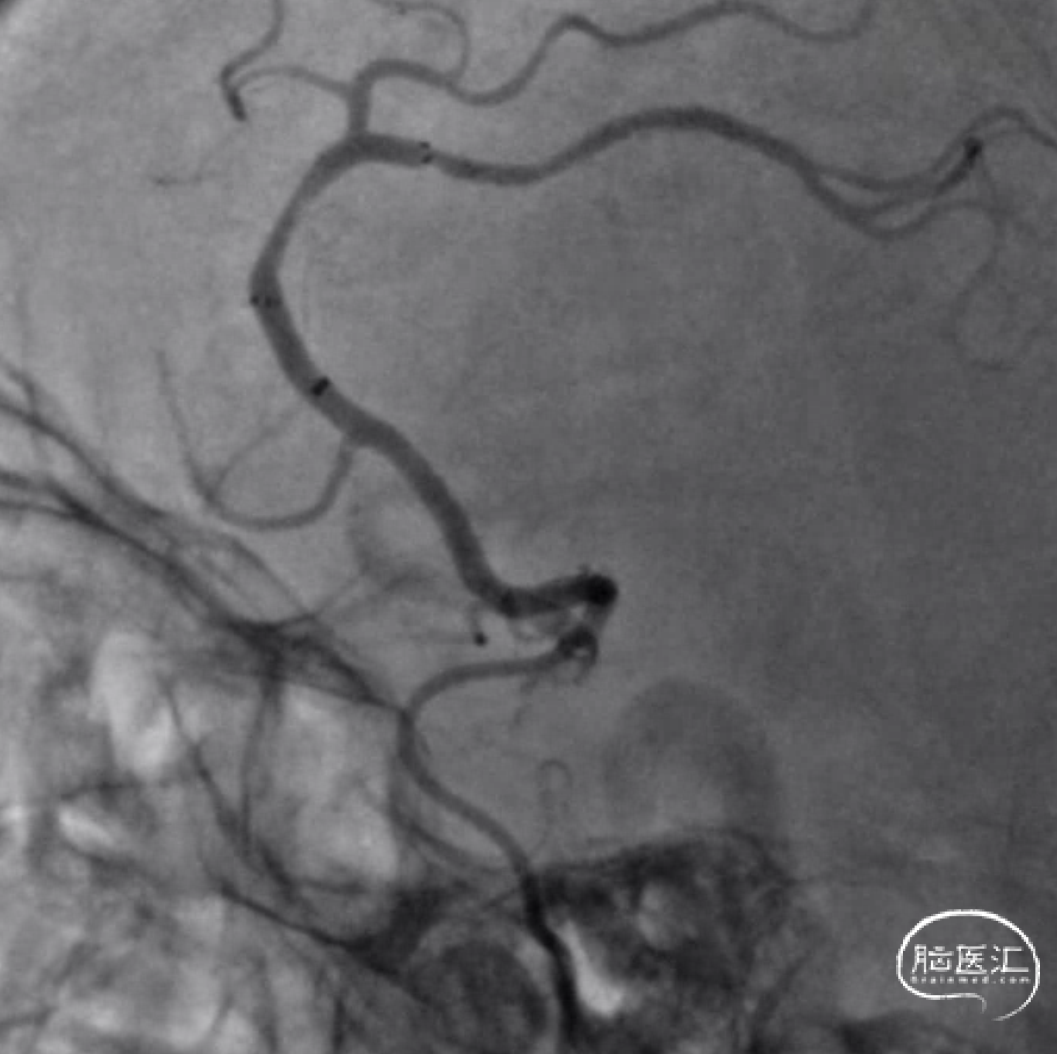

DSA:

取栓后即刻造影。

15min后复查造影,明显回缩。

加奇SacSpeed®球囊扩张导管2×9mm顺利到位。

缓慢扩张至5atm后造影。

15min后复查造影,血流维持可。